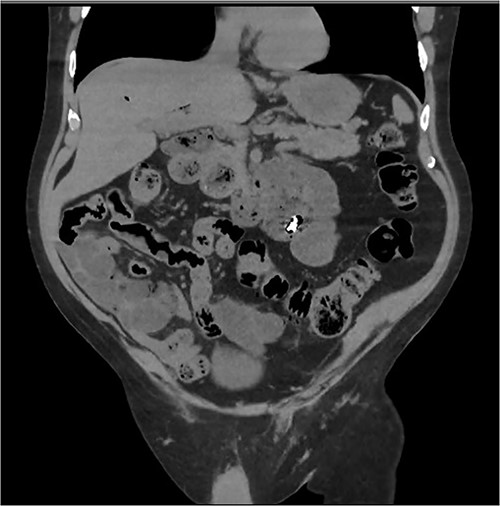

An 80 year old male presented to the emergency department after accidentally swallowing his hearing aids. On presentation he was pain free, hemodynamically stable, and had a soft abdomen. He had a background of type-2 diabetes, rheumatoid arthritis and diverticulitis. The hearing aids were powered by lithium battery. X-ray found two foreign bodies in the left upper abdomen (Fig. 1). After assessment in the emergency department, he returned home to await their natural passage. One hearing aid was found in his stools the following day, but he represented three weeks later as the second hearing aid remained unaccounted for. He underwent repeat abdominal x-ray and CT, which found the hearing aid retained within a presumed distal duodenal diverticulum (Figs 2 and 3). He was booked a push enteroscopy the following day.

Abdominal X-ray identifying two hearing aids on day of initial presentation.